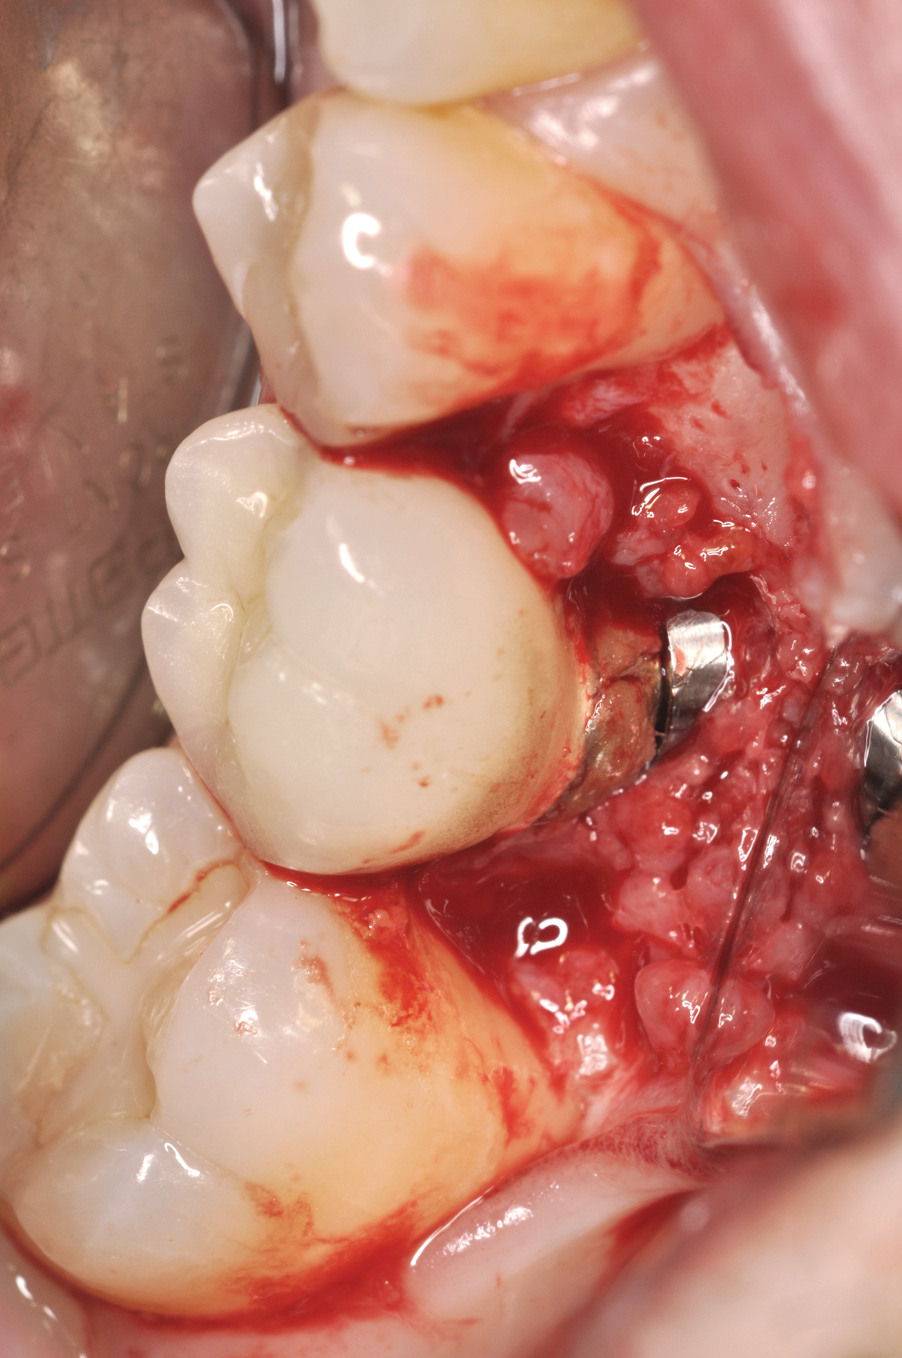

Fig 8. Loss of restoration and subsequent tissue overgrowth from broken abutment screw as shown in the radiograph (Fig 9).

Figure 8

Fig 9. Radiograph depicting fractured screw inside of the implant.

Figure 9

Fractured screws are challenging to retrieve, particularly when they are abutment screws. If the screw head is accessible, a hemostat can be used to remove it. However, when the screw breaks inside the implant (Figure 8 and Figure 9), removal can be highly complicated in order not to damage the implant’s internal threads. Therefore, many implant manufacturers have developed screw-retrieval kits. Because it is critical to be able to visualize the area, magnification using loupes and a surgical microscope may be necessary.8 Additional methods can be used to remove the fractured screw. A ¼ round bur set on a high speed can be used by lightly activating it, touching only the side of the screw. After repeating this technique several times, the screw may be able to be backed out with an explorer tip. Ultrasonic tips with copious irrigation may also dislodge the screw.7,20 In cases in which this fails, a small slot can be made in the head of the screw to back it out.21 If screw threads have been damaged during retrieval, they may be retapped using a tool obtained only from the implant manufacturer.7